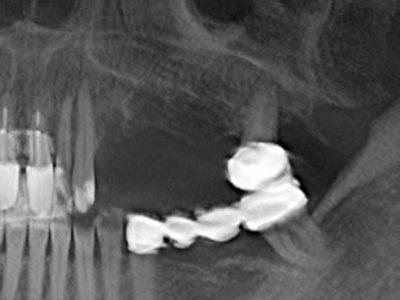

Когато се извършват хирургични процедури върху кост в непосредствена близост до чувствителни структури като кръвоносни съдове или нерви, ротиращите инструменти създават значителен риск за ятрогенно нараняване. Пиезоелектрическите апарати могат да бъдат от помощ при препарация на костно покритие и отстраняване на твърда кост близо до нерви, особено за оголване на нервите след ятрогенно нараняване, както и по време на латерализация на нервите за резекционни и реконструктивни процедури или поставяне на имплант (Фиг. 17-20). Лекият контакт между пиезонакрайника и нерва по принцип не води до нараняване, но ако действате непредпазливо с трионообразни движения или приставки за остатъчен костен субстрат, може да причините временно или перманентно увреждане на нерва. Въпреки това, рискът от увреждане се счита за много по-малък, отколкото при употреба на триони или ротиращи инструменти (Pereira, Gealh et al. 2014).